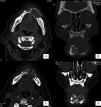

Se solicitó una tomografía computarizada (TC), donde en sus imágenes axiales se apreció una lesión hipodensa de aspecto multilocular que se extendía desde la región correspondiente a la zona del canino derecho hasta la región contralateral correspondiente al primer molar izquierdo que generaba abombamiento, adelgazamiento y perforación de tablas óseas (fig. 1a y b). Se programó biopsia incisional e instalación de tubo de drenaje con el fin de descomprimir la lesión.

a) TAC corte axial. Se observa extensa lesión que genera abombamiento, adelgazamiento y perforación de tablas óseas. b) TAC corte coronal, se muestra compromiso del borde basilar mandibular. TAC corte axial (c) y coronal (d) 3 meses posterapia descompresiva. Se observa una mayor extensión de la lesión y franca destrucción de tablas óseas.

Con este diagnóstico se decidió continuar con la terapia descompresiva y controlar a la paciente. Tras 2 semanas, la paciente presentó dolor e impotencia funcional que fue en aumento hasta impedir su alimentación tras 2 meses de instalado el drenaje. Con esta evolución se solicitó una nueva TC en la cual pudo confirmarse que la terapia descompresiva no cumplía con su objetivo, ya que se observó un aumento del compromiso de los tejidos producto de la lesión, con relación a las condiciones previas, presentando franca destrucción de tablas óseas tanto vestibular como lingual (fig. 1c y d). Luego de 3 semanas de ejecutado el procedimiento de descompresión, y teniendo en cuenta los nuevos hallazgos clínicos y radiofráficos, se realizó la excéresis de la lesión más curetaje y aplicación de solución de Carnoy durante 30 s en el lecho operatorio. El defecto óseo subyacente fue reconstruido mediante la utilización de una placa de reconstrucción mandibular. La pieza quirúrgica se envió a estudio histopatológico el cual informó la presencia de una membrana quística con tejido epitelial anaplásico, observándose pérdida de la estratificación epitelial, pleomorfismo celular y nuclear, pérdida de la relación núcleo/citoplasma, nucléolos prominentes, entre otros (fig. 2b). La proliferación neoplásica presentaba un patrón infiltrativo hacia el tejido conjuntivo subyacente (fig. 2c). En otros sectores de la muestra se observaron nidos e islotes de proliferación epitelial en el espesor de la pared quística, que mostraron las mismas características anaplásicas (fig. 2d). En función de estos hallazgos histopatológicos se emitió el diagnóstico de carcinoma de células escamosas intraóseo moderadamente diferenciado.